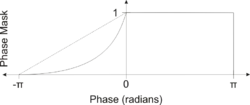

The values in the phase images are constrained from -π to π so if the value goes above π it wraps to -π, inhomogeneities in the magnetic field cause low frequency background gradients. This causes all the phase values to slowly increase across the image which creates phase wrapping and obscures the image. This type of artifact can be removed by phase unwrapping or by high pass filtering the original complex data to remove the low frequency variations in the phase image.

The susceptibility weighted image is created by combining the magnitude and filtered phase images. A mask is created from the phase image by mapping all values above 0 radians to be 1 and linearly mapping values from -π to 0 radians to range from 0 to 1, respectively. Alternatively, a power function (typically 4th degree) can be used instead of a linear mapping from -π to 0 to increase the effect of the mask. The magnitude image is then multiplied by this mask. In this way phase values above 0 radians have no effect and phase values below 0 radians darken the magnitude image. This increases the contrast in the magnitude image for objects with low phase values such as veins, iron, and hemorrhage.